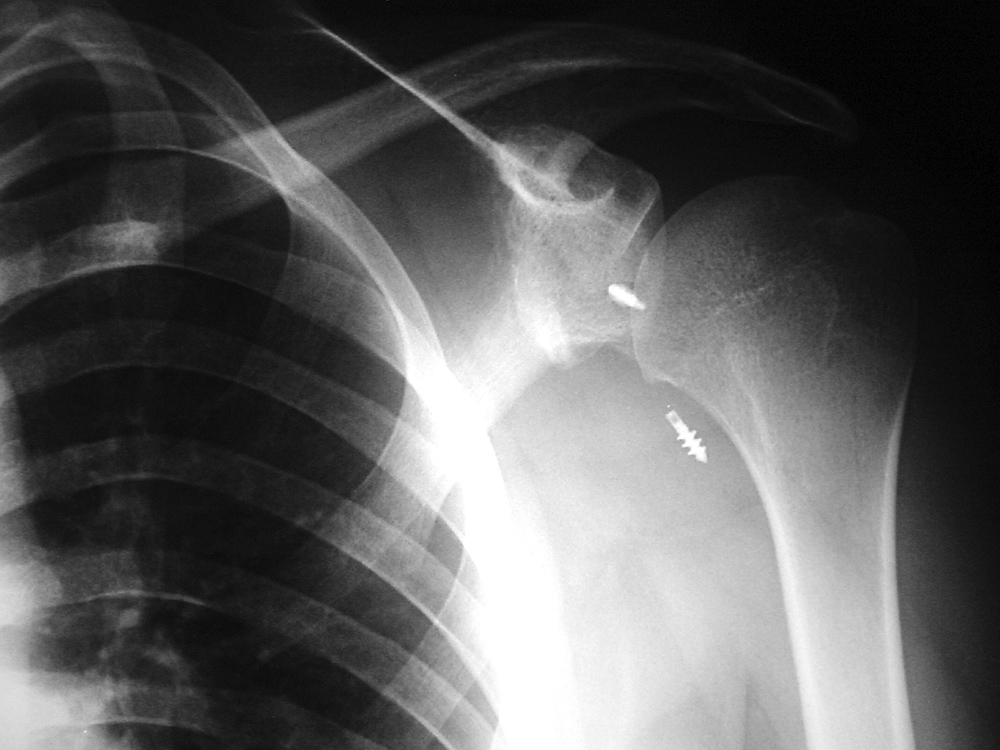

| 41 year-old man with chronic left femoral neck fracture and fracture of superior cannulated fixation screw. The partially visualized intramedullary nail is for an old femoral shaft fracture. |